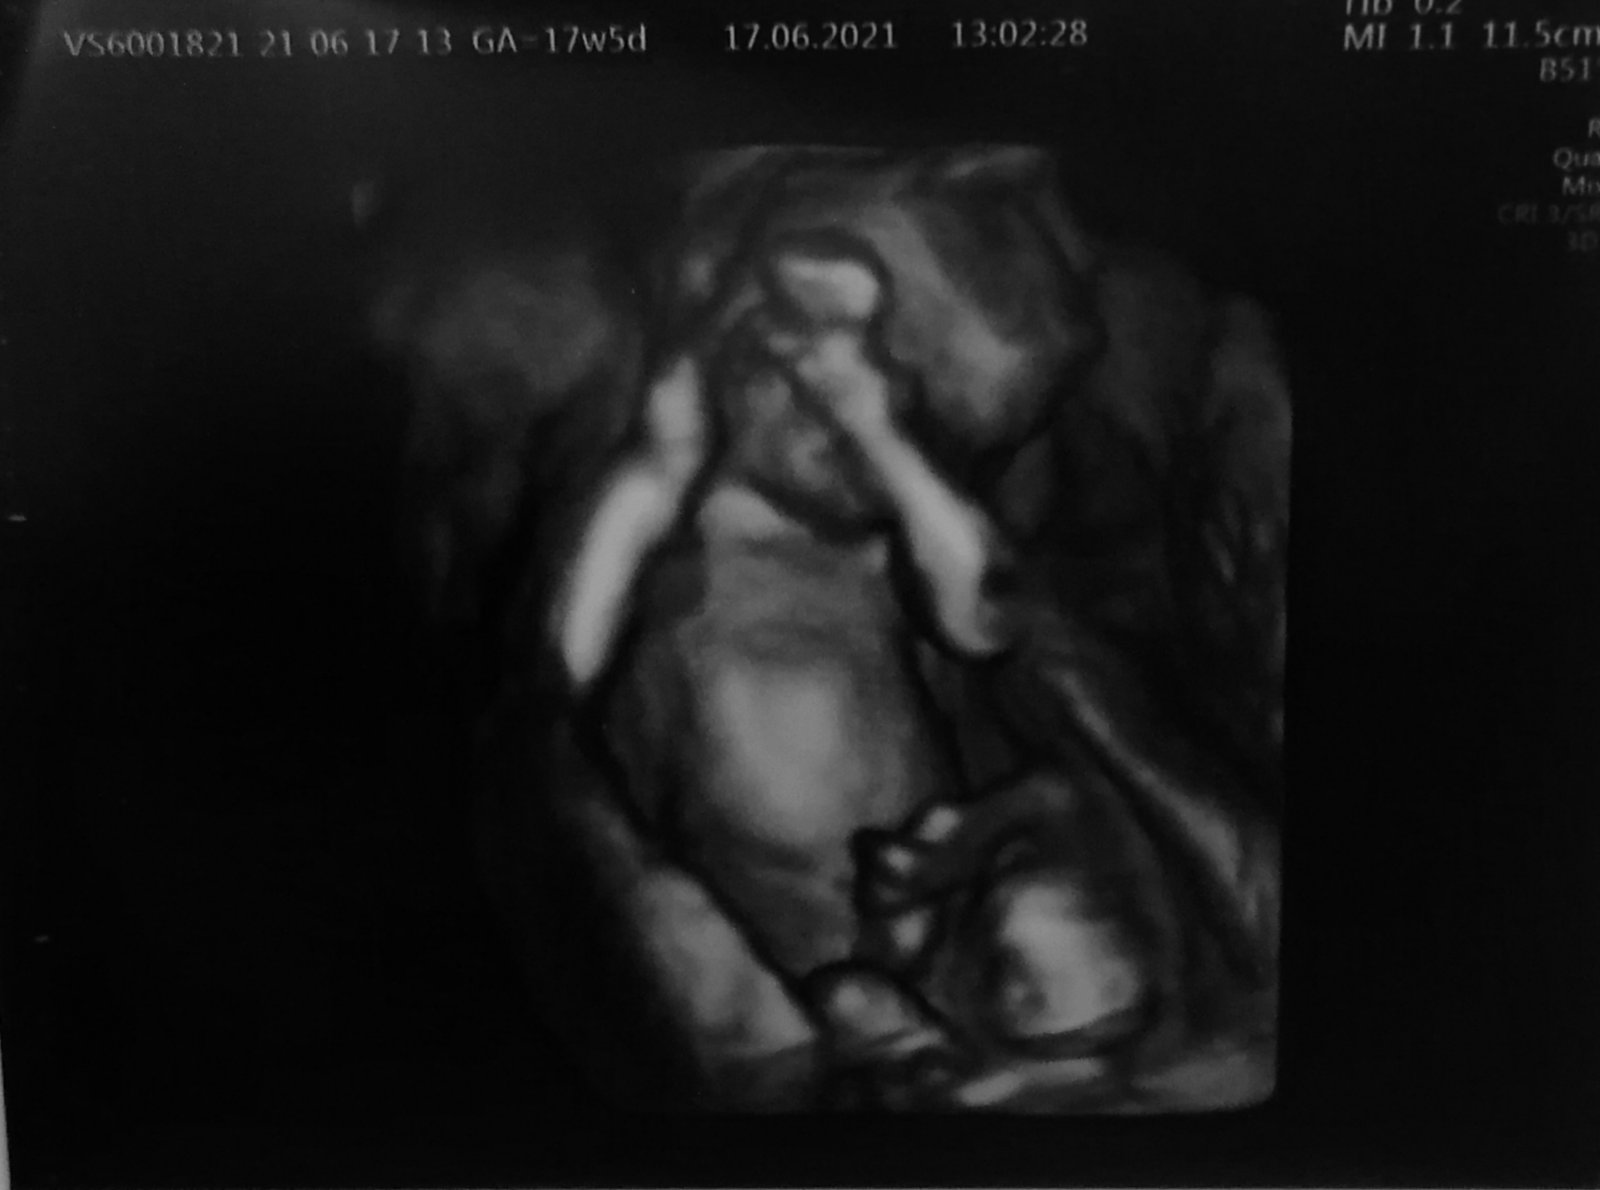

@hafanana25 ahooj ako ste dopadli co vám povedali na konzultácii? Ja som bola na krvných testoch a Sone vo štvrtok kvôli vrodeným chorobám. Ak by boli zle vysledky z krvi bude ma kontaktovať lekárka v pondelok. Bože tak dúfam ze nebude volať 🙏🏼 už nám vedela povedať vo štvrtok že čakáme chlapčeka 💙💙💙 manžel si ho asi vymodlil 😂💙 rastie vraj rovnomerne, (akurát je týždeň dopredu 😁 a to vlastne od začiatku) merala mu časti tela, ukázala nám aj obličky, močový mechúr, žalúdok, prsteky a tak bolo to zaujímavé, už je to malý človiečik. Už len dúfame že testy budú ôk. Drz nám palce aby sme to dobojovali, pred týždňom som brala aj antibiotika kvôli gyno problémom, po dobrat zas som mala tak mam teraz len rosalgin aby sme nedávali stále antibiotika, bože všetko sa na mňa lepi ale dúfam veľmi dúfam ze to dobre dopadne. Už týždeň beriem aj lieky na štítnu žľazu 😂🤦🏼♀️ takže všetko všetko. Ale tak co by sme nevydržali hlavne nech testy a bábätko sú v pohode už by sa mi zišlo troska kľudu a ukludnenia dušičky.

@hafanana25 ahooj tak zatiaľ sa držíme a musím si zaklopať už nejaký ten piatok bez krvácania. 💙 13.7 nás čaká morfologicky ultrazvuk dúfam ze bude všetko ôk, krvne testy nám vyšli zatiaľ vždy dobre 🙌🏼💙 na foto sa zatiaľ zakrýva 😃 asi bude po tatovi😃😃 chudáčik ešte je ako malý votrelček😃 ale strašne sa teším z prvých pohybov ktoré mam asi posledné 3-4 dní 💙a vy ste ako na tom?